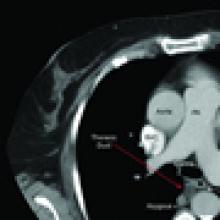

General anesthesia with single lung ventilation is required and the duct is always approached through the right chest due to its constant position in the lower right chest (Figure 1). The patient is placed in a left lateral decubitus position, rolled forward, and flexed to allow increased exposure of the posterior mediastinum. An epidural is not necessary and intercostal blocks with 0.25% bupivacaine can be used for analgesia. The thoracoscope is placed in the seventh intercostal space along the line of the anterior superior iliac spine and the working incision (5cm) is placed in the fifth or sixth intercostal space in the anterior axillary line (Figure 2). The soft tissues of the chest wall are kept open with a Weitlaner retractor and the intercostal incision is made longer than the skin incision. This allows for the introduction of two or three instruments through this incision and allows suction to be applied within the chest without causing re-expansion of the lung. A third incision is made at the level of the dome of the diaphragm after visualizing the desired space thoracoscopically. This incision is placed along the mid-axillary line.

| Figure 1: CT Chest showing thoracic duct. | Figure 2: Thoracoscopic port placement. | Figure 3: Inferior Pulmonary Ligament Division. |